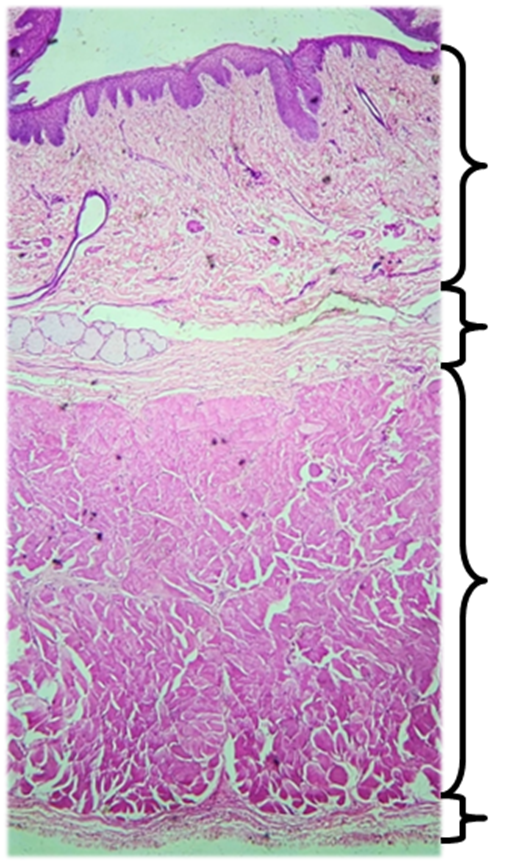

Lab Activity 8.2: Histological Examination of Digestive OrgansThe organs of the digestive tract have four basic tissue layers: the mucosa, submucosa, muscularis, and serosa. The mucosa, the deepest layer, is composed of epithelial tissue and faces the lumen of the GI tract. The submucosa is the next layer of tissue surrounding the mucosa and is composed of connective tissue and glands. The muscularis is composed of smooth muscle and may be oriented in circular or longitudinal direction. The final, superficial layer is the serosa (or adventitia in the esophagus) composed of connective and epithelial tissue.

3. Observe the following histology images and determine if they came from the stomach, esophagus, or intestine. Then identify the following structures on the histology images provided on the following page: serosa/adventitia, longitudinal muscularis, circular muscularis, submucosa, mucosa

Figure 8.5 Histology Images of the esophagus, stomach, and intestine (not in order). Photographs taken by Gina Profetto